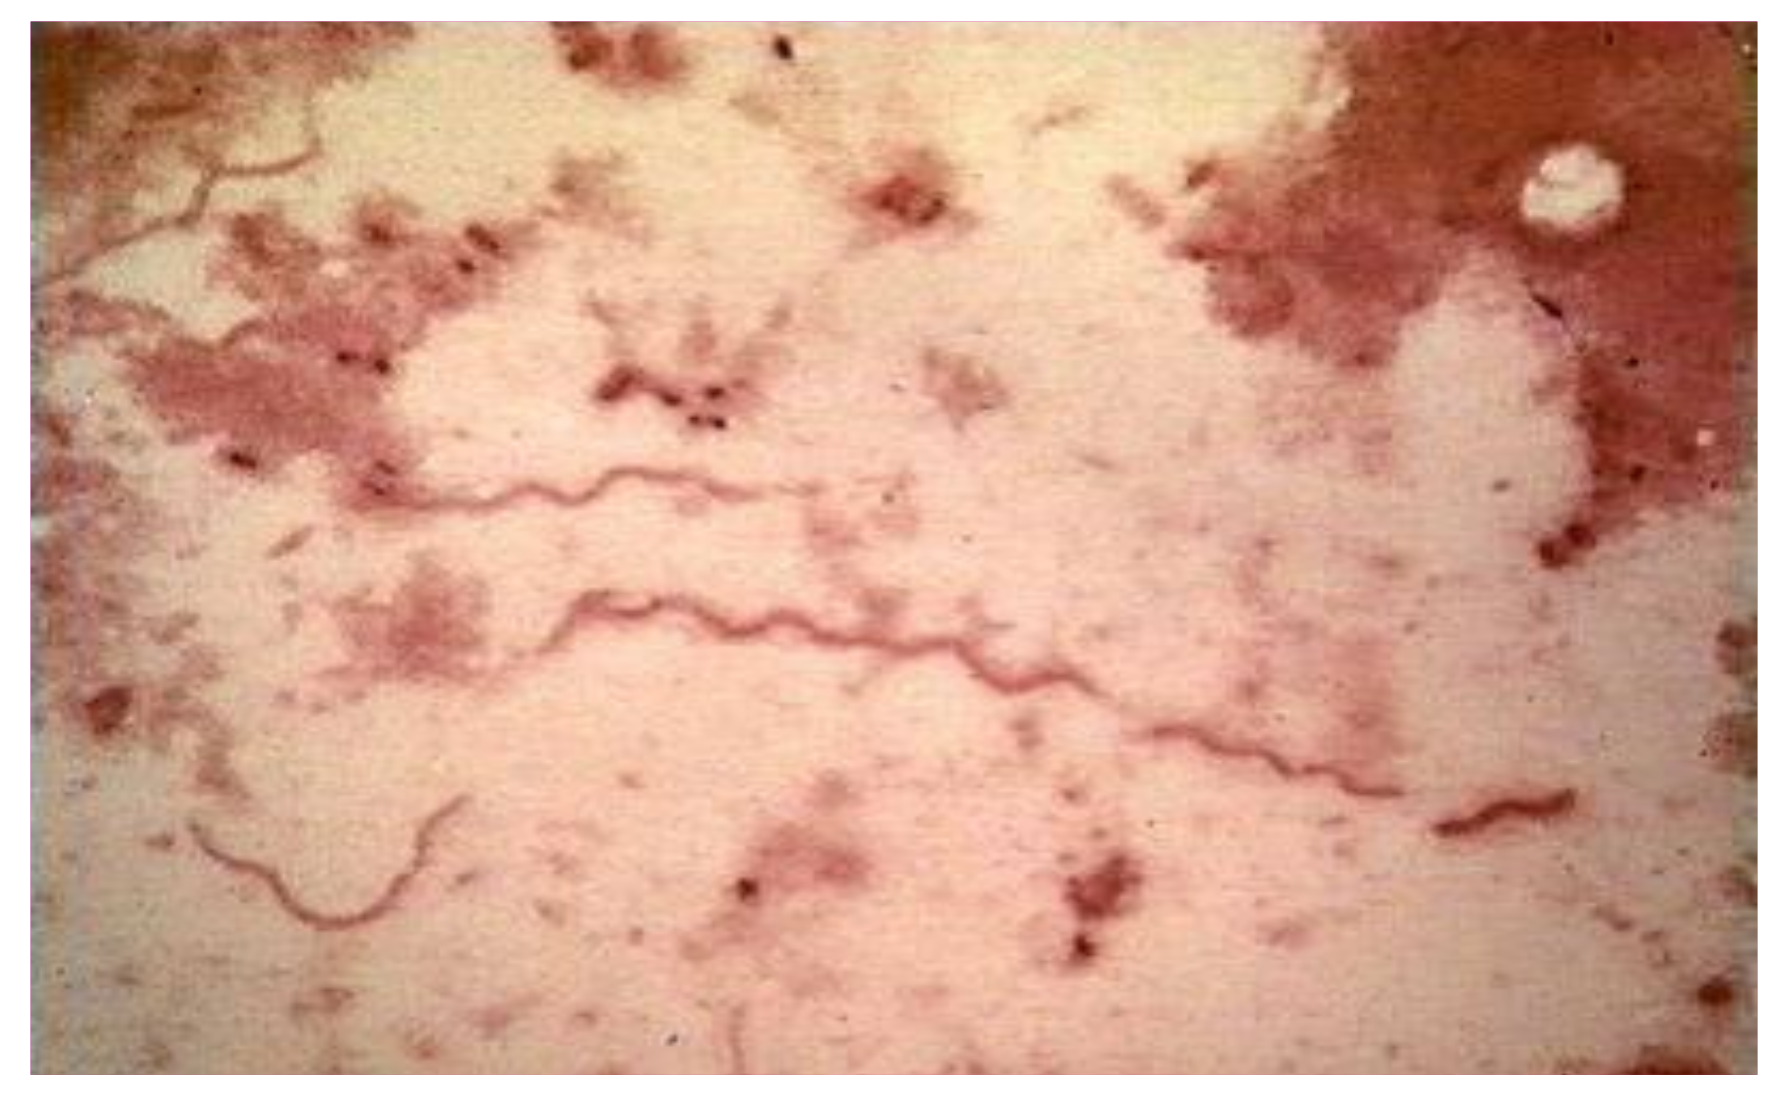

| Characteristic | Detail |

|---|---|

| Microaerophilic | |

| Shape | Spiral |

| Bacterial body length | 7–24 µm |

| Width | 0.20–0.50 µm |

| Propeller pitch | 1.7–3.3 µm |

| Number of flagella | 7–12 |

| Peripheral sheath | Absent |

| Three-layer surface membrane | It envelops a periplasmic space, containing flagella and the protoplasmic cylinder |

| Cytoplasmic tubules | Absent |